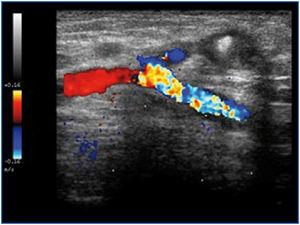

Mujer de 78 años en programa de hemodiálisis desde 2009 a través de una FAV humerocefálica izquierda. La paciente presenta un edema en brazo, que le provoca dolor progresivo e impotencia funcional. Diagnosticada de oclusión de vena subclavia con varios intentos de ATP con recidiva precoz, se decide colocación de catéter venoso central derecho y cierre de la FAV por mal funcionamiento. Se consigue anulación de la FAV mediante inyección ecoguiada de trombina (figura 1) en la cefálica con trombosis de esta. A los 10 días el edema ha desaparecido, estando la arteria permeable y la paciente asintomática.

Figura 1. Anastomosis humerocefálica tras inyección de trombina